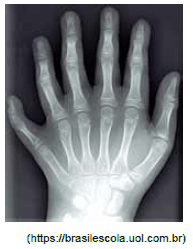

A figura apresenta a radiografia da mão de uma menina portadora de polidactilia, uma anomalia genética que consiste na alteração quantitativa anormal dos dedos das mãos (quirodáctilos) ou dos pés (pododáctilos).

Na família dessa menina, seu pai e seus avós paternos são portadores da mesma característica, mas não sua tia e seu tio, únicos irmãos de seu pai. A mãe e o único irmão dessa menina não apresentam essa característica.

O tipo de herança dessa característica e a probabilidade de que os pais da menina tenham um terceiro filho do sexo biológico masculino e com polidactilia são: